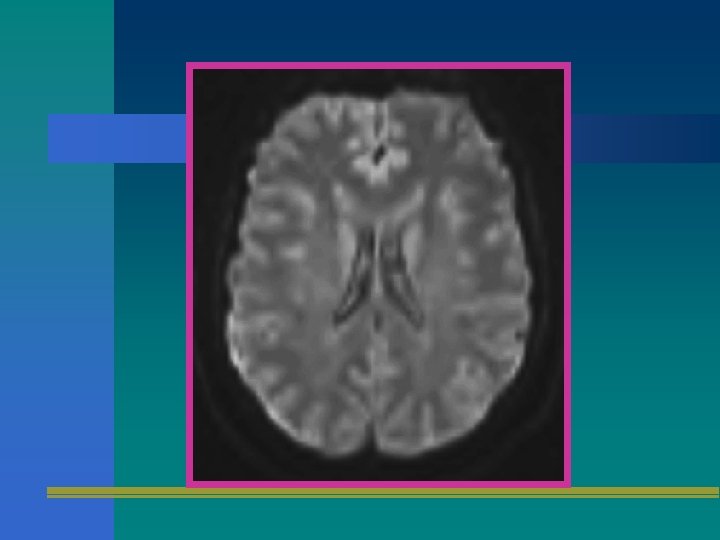

DWI • DIFFUSION WEIGHTED IMAGE • MIDE LA DIFUSION DE AGUA EN TEJIDOS BIOLOGICOS. • ES UTIL PARA MEDIR DISRRUPCIONES TEMPRANAS DE LA BARRERA HEMATOENCEFALICA Y PARA DETERMINAR TRAYECTOS AXONICOS (TRACTOGRAFIA)